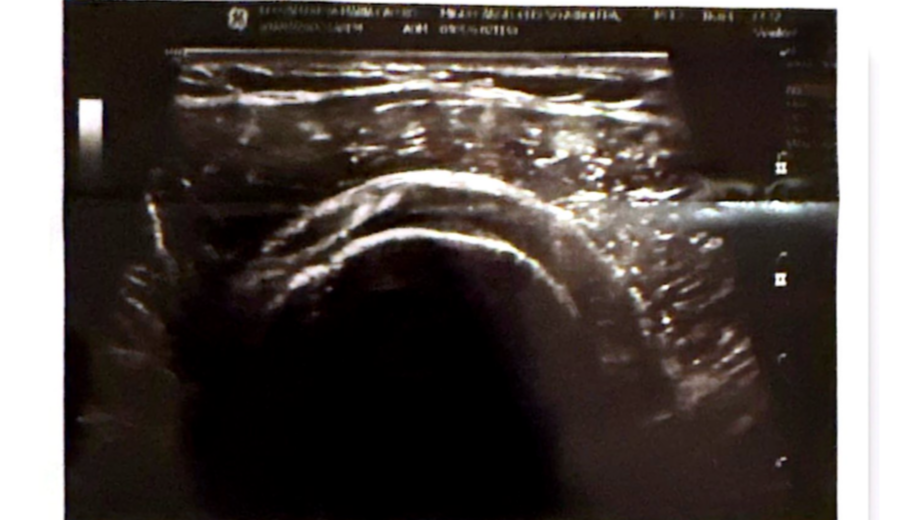

Tengo 24 años y siempre he sido una persona independiente y activa. Mi trabajo en tecnología y mi pasión por el deporte dependen totalmente de mi capacidad física. Sin embargo, hoy enfrento una situación que me ha obligado a detenerme: una rotura total de uno de los tendones principales de mi hombro, que ha comenzado a afectar seriamente la fuerza y estabilidad de mi brazo.

Lo que empezó como una lesión se ha vuelto algo mucho más serio. La lesión en mi hombro me ha provocado debilidad progresiva en mi brazo, episodios de hormigueo y temblores en mi mano, y un dolor constante en el hombro que se siente como una punzada profunda al intentar mover el brazo. Esto está afectando seriamente mi capacidad para trabajar y realizar actividades cotidianas. Ver cómo pierdo poco a poco la fuerza en mi herramienta de trabajo ha sido un golpe muy duro. Los médicos me han explicado que el tiempo es nuestro mayor enemigo; si no me opero pronto, la recuperación podría volverse mucho más difícil y podría perder la posibilidad de recuperar el movimiento normal de mi brazo.

I am 24 years old, and I have always been an independent and active person. My work in technology and my passion for sports depend entirely on my physical capabilities. However, today I face a situation that has forced me to stop: a full tear of one of the main tendons in my shoulder, which has begun to seriously affect the strength and stability of my arm.

What started as an injury has become something much more serious. The damage to my shoulder has caused progressive weakness in my arm, episodes of tingling and tremors in my hand, and constant shoulder pain that feels like a deep stab whenever I try to move. This is seriously affecting my ability to work and perform daily activities. Watching myself slowly lose strength in my primary 'work tool' has been a devastating blow. Doctors have explained that time is our greatest enemy; if I don't have surgery soon, recovery could become much more difficult, and I could lose the chance to regain normal movement in my arm.